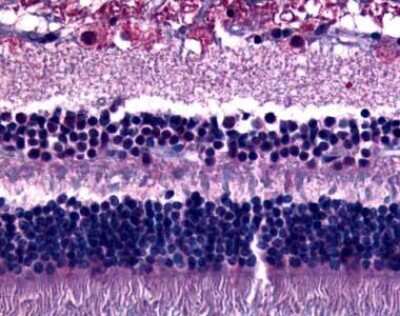

Immunohistochemistry-Paraffin: GPR75 Antibody [NLS3252] - Analysis of anti-GPR75 antibody with retina.